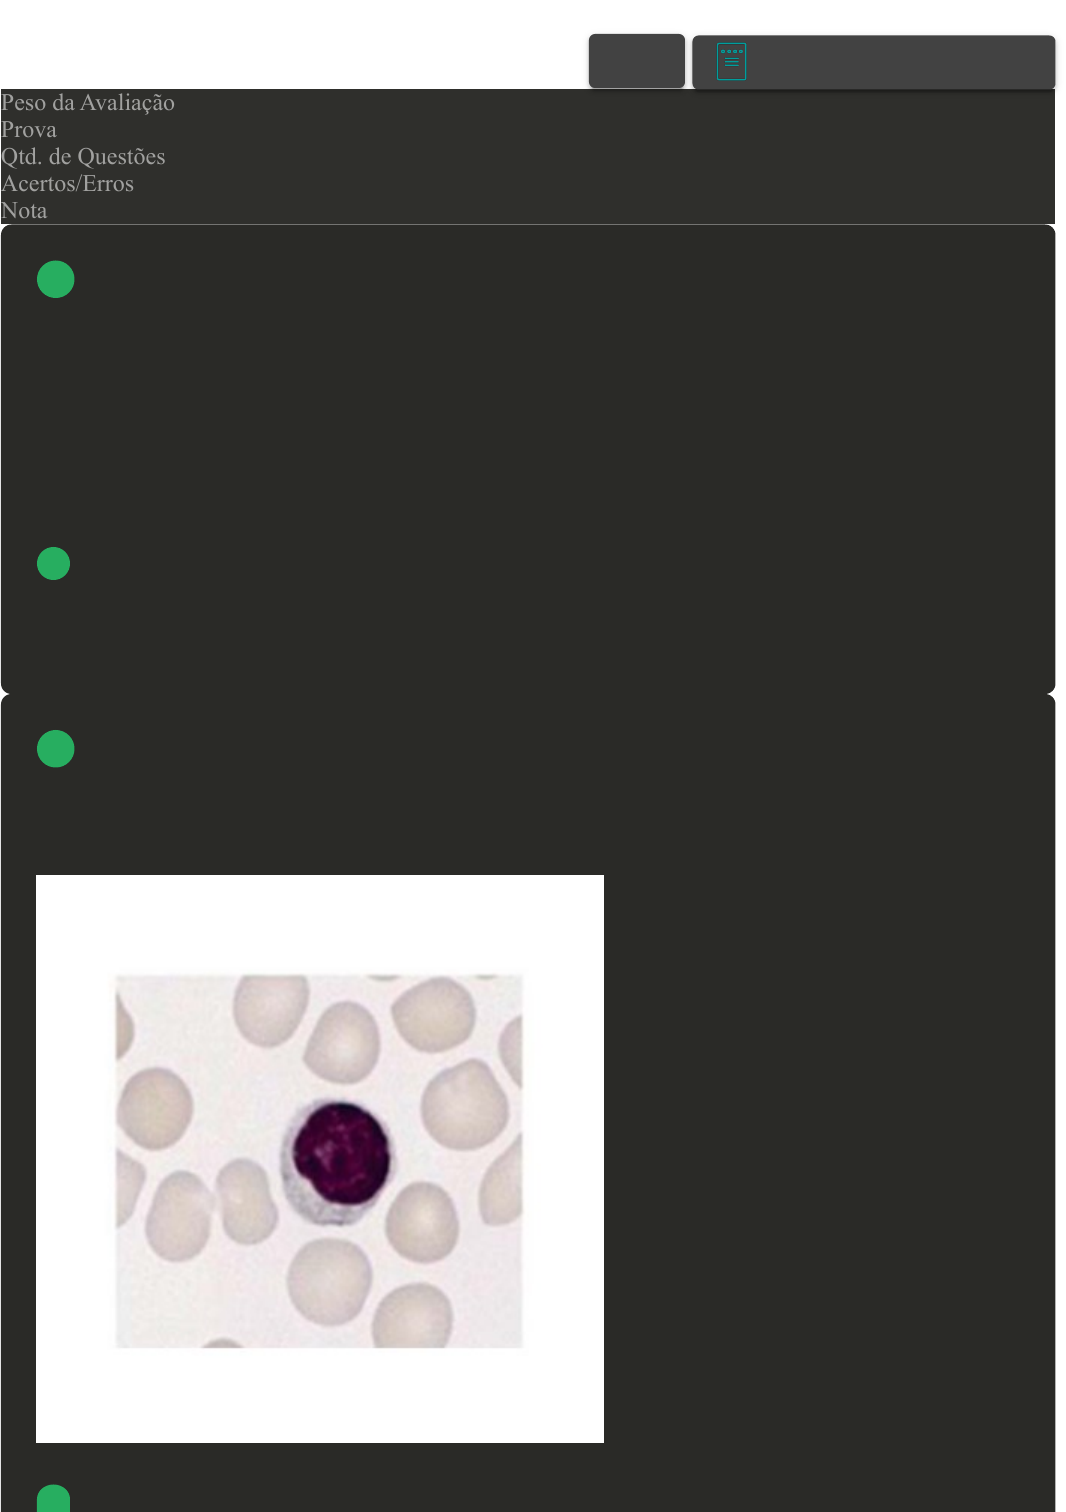

Os leucócitos, também conhecidos como glóbulos brancos, são células presentes no sangue e

produzidas na medula óssea e no tecido linfático. São responsáveis pela defesa do nosso organismo

contra patógenos.

Com base no tipo de leucócito apresentado na imagem anexa, assinale a alternativa CORRETA:

Linfócito.

B Monócito.

C Neutrófilo.

D Basófilo.